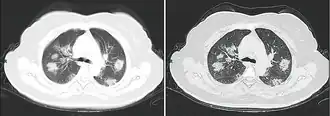

КТ грудной клетки иногда может помочь идентифицировать и охарактеризовать патологию лёгких и дать неспецифические результаты при инфекции COVID-19. Систематический обзор результатов компьютерной томографии грудной клетки у 919 пациентов описал типичное раннее проявление COVID-19 как «двустороннее мультилобарное помутнение матового стекла (GGO) с периферическим или задним распределением».[19] Одно исследование показало, что чувствительность КТ к инфекции COVID-19 составила 98 % по сравнению с чувствительностью ОТ-ПЦР на 71 %; однако это было сделано в китайской провинции Ухань и не подлежит обобщению.[20] Наиболее распространёнными результатами компьютерной томографии были двустороннее затухание матового стекла (пятнистое или рассеянное) с субплевральным доминированием, сумасшедшей укладкой и консолидацией на более поздних стадиях.[21] Эти данные являются неспецифичными и обнаруживаются также при других типах пневмонии. Небольшое исследование показало, что китайские рентгенологи продемонстрировали чувствительность 72-94 % и 24-94 % в дифференцировании COVID-19 от других типов вирусной пневмонии с использованием компьютерной томографии.[22] Ни одно исследование ещё не подтвердило точность и дискриминационную ценность компьютерных томографий, чтобы отличить COVID-19 от других вирусных пневмоний. Поэтому CDC не рекомендует КТ для первоначального скрининга, как подчёркивалось в звонке COCA в четверг, 5 марта. Люди с подозрением на COVID-19 должны проходить ОТ-ПЦР, которая является наиболее специфическим тестом.[23]

Компьютерная томография стадии быстрого прогрессирования